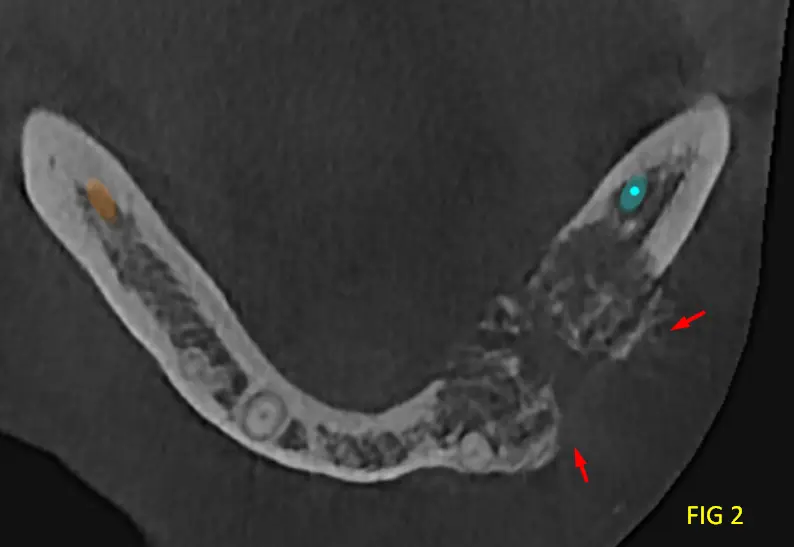

En las reconstrucciones 3D y cortes multiplanares (ver Fig 1, 2 y 3) se observa lesión oseteolítica extensa con ausencia de una capsula definida, ubicada en el cuerpo mandibular, lado izquierdo, zona de premolares.

Presenta tabiques óseos finos que delimitan compartimentos irregulares con expansión y adelgazamiento de las corticales óseas, con áreas de compromiso cortical. La relación cercana con el conducto dentario inferior, sin evidencia clara de invasión, pero con desplazamiento y borramiento en sectores de dicha pared del conducto.

En cortes transversales se aprecia la naturaleza infiltrativa de la lesión, con forma de rayos de luz, sin límites netos, característica típica del mixoma Odontogénico.